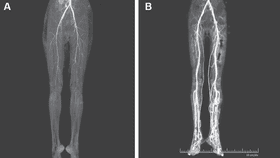

When the doctors examined her, they found her legs were cold to the touch and they were unable to feel a pulse in the popliteal and dorsalis pedis arteries, which supply blood to the lower legs and feet. A computed tomography (CT) scan showed narrowing of the arteries, after which she was given a blood thinner – heparin. The pain in her legs improved and her legs got warmer as the blood flow increased. Unfortunately, one of her toes had to be amputated due to gangrene.

Two weeks after treatment and ceasing to take the medication, the blood flow in her legs improved.